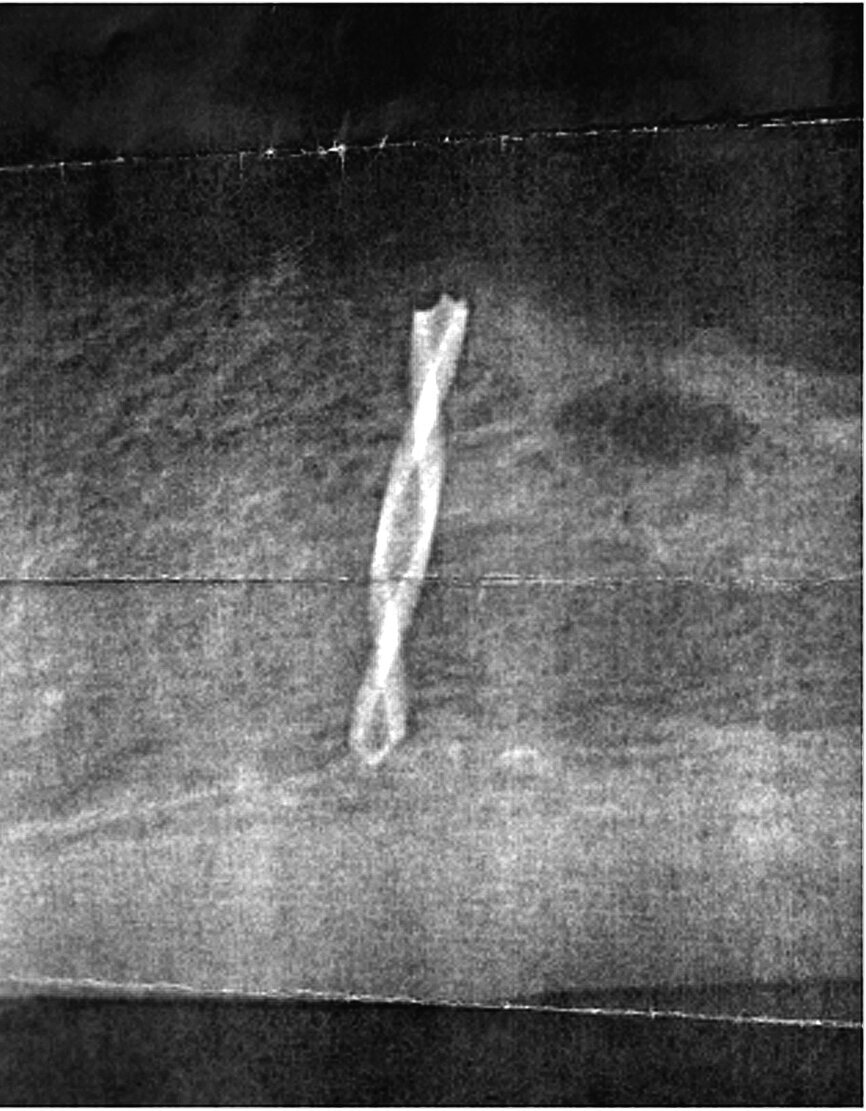

Upon drilling the initial pilot osteotomy preparation directly through the soft tissue, the drill immediately broke ‘in the bone’. A periapical radiograph confirmed that the drill was broken and deemed to be ‘in the bone’. The subsequent paper print-out of the digital radiograph can be seen in Figure 6. The clinician reported what happened to the patient and decided to abort the entire procedure and send the patient to a nearby oral and maxillofacial surgeon. The surgeon examined the patient and decided to let the area heal, and follow-up later for a new plan of treatment. At this time a CBCT was performed by the oral surgeon to better assess the situation. The patient was not pleased, lost confidence in the clinician, and sought another opinion.

Fig. 6: Reveals the broken pilot drill ‘in the bone’.

The broken drill was immediately located lingual to the alveolar crest embedded in the soft tissue. Apparently, the drill deflected off the sharp ridge into the floor of the mouth, and the torque caused the drill to break. Fortunately, the drill did not cause any immediate complications as the floor of the mouth contains many vessels, which if perforated, could have resulted in a sublingual hematoma. The remaining broken drill as seen in Figure 14 was easily retrieved.